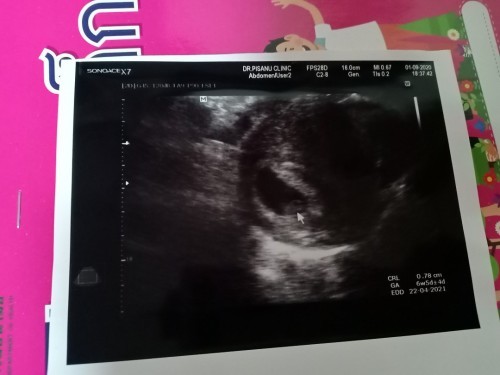

บ้านนี้ซาวด์ป่านหน้าท้อง6วีค5วัน เจอพร้อมเสียงหัวใจน้องค่ะแม่ รอหน่อยนะแม่บางทีไข่ตกช้า

อัลตราซาวด์ครั้งแรก 8 วีคผ่านช่องคลอด เจอตัวอ่อนและเสียงหัวใจชัดเจนค่ะ

บ้านนี้ตอน 7 วีค เจอแต่ถุง. พอ9 วีค เจอเลยค่า รูปตอน 7 วีคคะ